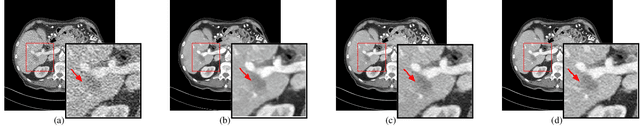

Abstract:Low Dose Computed Tomography (LDCT) is widely used as an imaging solution to aid diagnosis and other clinical tasks. However, this comes at the price of a deterioration in image quality due to the low dose of radiation used to reduce the risk of secondary cancer development. While some efficient methods have been proposed to enhance LDCT quality, many overestimate noise and perform excessive smoothing, leading to a loss of critical details. In this paper, we introduce D-PerceptCT, a novel architecture inspired by key principles of the Human Visual System (HVS) to enhance LDCT images. The objective is to guide the model to enhance or preserve perceptually relevant features, thereby providing radiologists with CT images where critical anatomical structures and fine pathological details are perceptu- ally visible. D-PerceptCT consists of two main blocks: 1) a Visual Dual-path Extractor (ViDex), which integrates semantic priors from a pretrained DINOv2 model with local spatial features, allowing the network to incorporate semantic-awareness during enhancement; (2) a Global-Local State-Space block that captures long-range information and multiscale features to preserve the important structures and fine details for diagnosis. In addition, we propose a novel deep perceptual loss, designated as the Deep Perceptual Relevancy Loss Function (DPRLF), which is inspired by human contrast sensitivity, to further emphasize perceptually important features. Extensive experiments on the Mayo2016 dataset demonstrate the effectiveness of D-PerceptCT method for LDCT enhancement, showing better preservation of structural and textural information within LDCT images compared to SOTA methods.